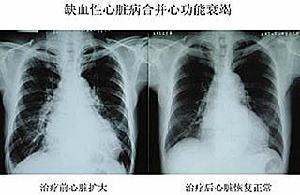

二、胸部X線檢查

主要表現為心影增大,且多數呈主動脈型心臟(以左心室增大為主、右心室多數正常) ,少數心影呈普大型。並可見升主動脈增寬及主動脈結鈣化等。多數患者有不同程度的肺淤血表現,但肺動脈段改變不明顯。充血型缺血性心肌病患者胸部X線檢查顯示心臟可有全心或左心擴大徵象,而限制型缺血性心肌病X線檢查心臟多不大,亦無心腔擴張。可有肺淤血、肺間質水腫及胸腔積液等徵象。有時可見冠狀動脈和主動脈鈣化。